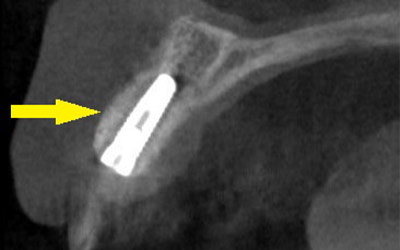

インプラントを埋入するために、骨を増やす方法はいくつかありましたが、この場合、患者様ご自身の骨をブロック状で移植するのが最も適していると判断し、自家骨移植術を行ないました。患者様ご自身の下顎前歯の下方から骨を採取して、骨がなかった部位に移植し、スクリューで固定したCT画像です。黄色矢印部分が、2つの骨片を移植して、固定したところです。

-

手術後の、別な方向からみたCT画像です。術前に大きく吸収されていた部分に、骨のブロックが移植され、骨が造成されています。真っ白にピンのように写るのは、骨を固定した小さなスクリューです。